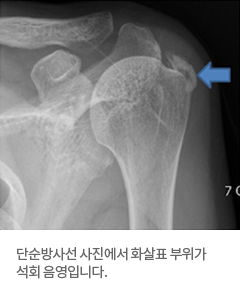

엑스레이 사진에서 어깨 주변에 뼈 음영과 비슷한 밀도의 하얀 석회가 관찰됩니다.

석회의 위치에 따라 전후면, 측면 및 액와 엑스레이 사진에서 보입니다. 양측에 발생하는 경우도 있습니다.

사진:단순방사선 사진에서 화살표 부위가 석회 음영입니다.